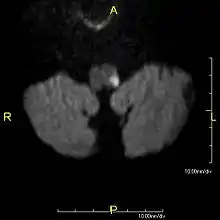

| Medulla oblongata, shown by a transverse section passing through the middle of the olive. (Lateral medullary syndrome can affect structures in upper left: #9=vagus nerve, #10=acoustic nucleus, #12=nucleus gracilis, #13=nucleus cuneatus, #14=head of posterior column and lower sensory root of trigeminal nerve and #19=Ligula.) | |